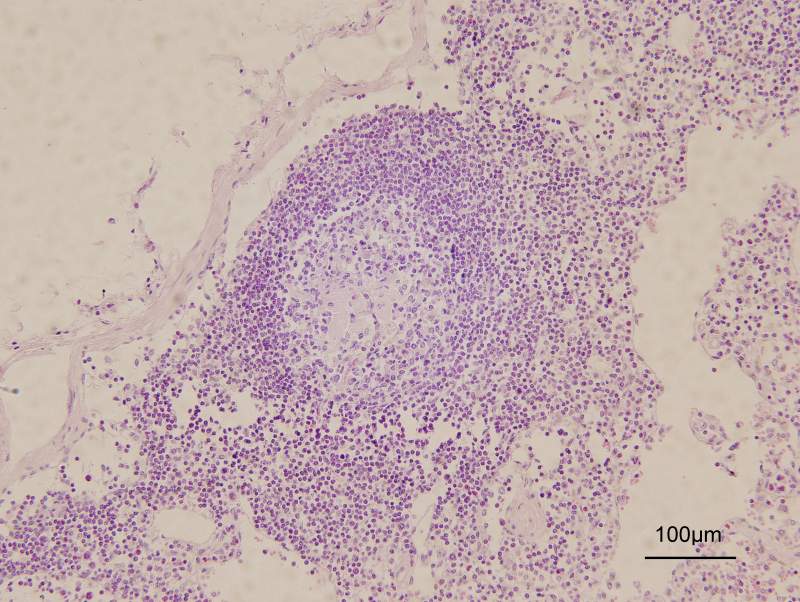

淋巴结内出现黄色颗粒和透明团块 已有1人参与